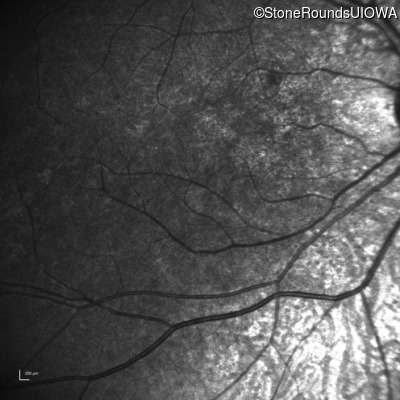

Infrared Fundus Photograph - Right - 5/200

Exemplar